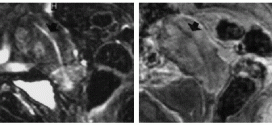

CÁNCER DE PRÓSTATA

El cáncer de próstata. Tumor maligno en general y especialmente el formado por células epiteliales. Publicado en: binipatia.com Escrito por: Salvador Gregori y Michelle Diggs Etiquetas: defender su propia vida, resultados Resumiendo: La próstata es una glándula que se encuentra debajo de la vejiga de los hombres y produce el líquido para el semen. El cáncer de próstata es común en hombres …